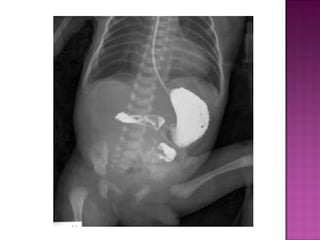

 On AXR gas filled distended stomach &

duodenal cap.

 Absent distal bowel gases,

 On AXRgas filled distended stomach & duodenal cap.  Absent distal bowel gases,